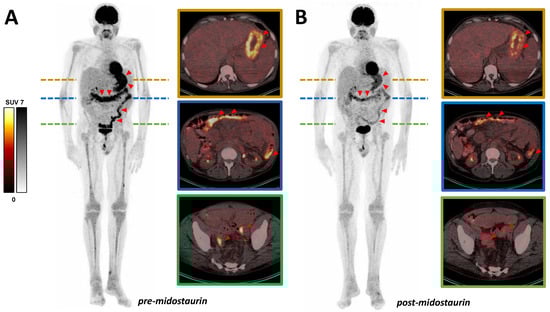

In this case, a 68-year-old man with formerly diagnosed malignant melanoma was admitted to our hospital for progression control of known SM (subtype: SM with associated hematologic neoplasm), including gastrointestinal manifestations. Manifestations of mastocytosis in the mucosa of the stomach, duodenum, and colon were confirmed histologically. In the course of the disease, the patient was treated with cetirizine, fexofenadine, and clemastine, as well as budesonide and prednisolone. Nevertheless, he developed a malabsorption syndrome with persistent diarrhea and a concomitant body weight loss of 25 kg. After failure of these treatments, therapy with midostaurin (200 mg per day) was introduced. No relevant side effects such as nausea, vomiting, neutropenia, anemia, or thrombocytopenia occurred during the therapy. Within the follow-up care for malignant melanoma, the patient received a [18F]FDG PET/CT pre- and post-initiation of midostaurin therapy (Figure 1). After 6 months’ therapy (6 therapy cycles, respectively) with midostaurin, [18F]FDG PET/CT revealed a substantially decreased multifocal tracer uptake in the known lesions in the gastrointestinal tract. Diffuse moderate uptake in bone marrow was also slightly regressive, while splenomegaly remained similar. According to imaging, the patient’s clinical condition improved significantly, with diarrhea markedly regressing and body weight increasing by approximately 15 kg. Consistently, a decrease in serum tryptase level (615.3 μg/L pre- vs. 21.9 μg/L post-midostaurin treatment) was noted. The declining [18F]FDG uptake of histologically confirmed manifestations of SM in the gastrointestinal tract during the course thus most likely represents a response to therapy with midostaurin.

Figure 1. Declining uptake can be seen in presented MIP (maximum intensity projection) and exemplary transversal slices of [18F]FDG PET/CT scan in gastrointestinal mastocytosis manifestations. (A) Baseline (blood glucose level: 87 mg/dL; hemoglobin: 11.2 g/dL) and (B) after 6 months’ therapy with midostaurin (blood glucose level: 103 mg/dL; hemoglobin: 11.5 g/dL). Exemplary SUVpeak values (pre- vs. post-midostaurin treatment): in stomach 7.2 vs. 5.8 and in colon 6.4 vs. 3.4. Diffuse uptake in bone marrow was also slightly regressive (exemplary in the left tibia SUVpeak 2.3 vs. 1.9), while splenomegaly remained similar. Red triangles exemplarily point to gastrointestinal mastocytosis manifestations.